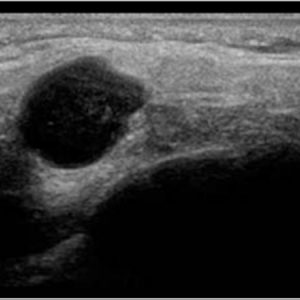

U tuyến nước bọt

Lượt xem: 170» 17-01-2021 -

U tuyến nước bọt

Lượt xem: 174» 17-01-2021 -

U tuyến nước bọt

Lượt xem: 149» 17-01-2021 -

U tuyến nước bọt

Lượt xem: 147» 17-01-2021 -

U tuyến nước bọt

Lượt xem: 146» 17-01-2021 -

U tuyến nước bọt

Lượt xem: 151» 17-01-2021 -

U tuyến nước bọt

Lượt xem: 146» 17-01-2021 -

U tuyến nước bọt

Lượt xem: 136» 17-01-2021 -

U tuyến nước bọt

Lượt xem: 132» 17-01-2021 -

U tuyến nước bọt

Lượt xem: 209» 17-01-2021 -

U tuyến nước bọt

Lượt xem: 150» 17-01-2021 -

U tuyến nước bọt

Lượt xem: 185» 17-01-2021 -

U tuyến nước bọt

Lượt xem: 151» 17-01-2021 -

U tuyến nước bọt

Lượt xem: 212» 17-01-2021 -